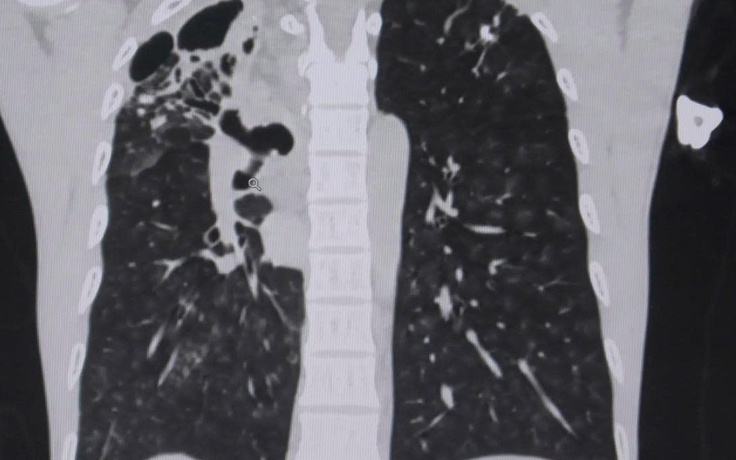

Anh V.V.H (49 tuổi, ở Tây Ninh) được đưa đến bệnh viện thăm khám sau khi ho ra máu. Các bác sĩ phát hiện anh bị biến chứng vỡ mạch máu phế quản sau thời gian lao phổi.

Cứu bệnh nhân Covid-19 ho ra máu nặng

Ho ra máu, nhập viện mới biết bị vỡ phình động mạch chủ ngực